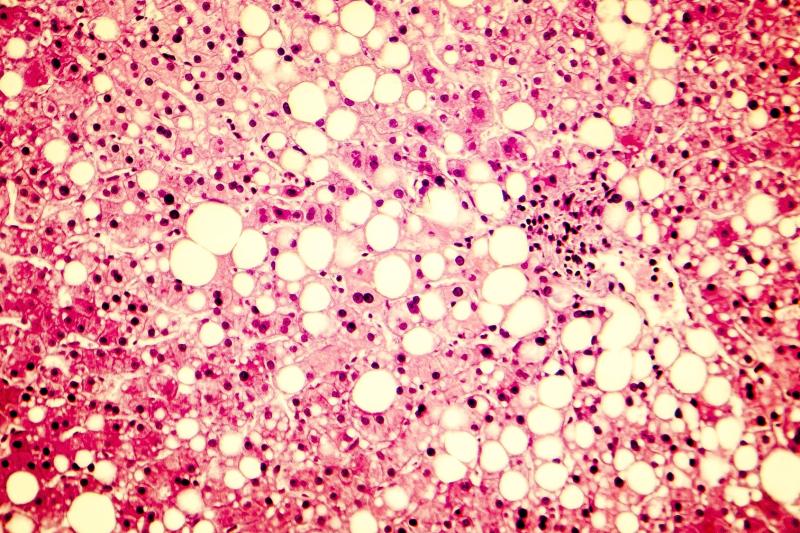

An RNA interference therapy, ARO-HSD, is tolerable at ≤200-mg doses, suggests a phase I/II study. Short-term treatment with ARO-HSD results in decreases in hepatic HSD17β13 mRNA and protein expression, which is complemented by alanine aminotransferase reductions.

Thirty-two normal health volunteers (NHV) and 18 patients with confirmed/clinically suspected nonalcoholic steatohepatitis (NASH) participated in this study. The authors then assessed the safety, tolerability, and pharmacodynamics of ARO-HSD among participants.

Double-blind NHV cohorts were treated with single escalating doses of ARO-HSD (25, 50, 100, or 200 mg) or placebo subcutaneously on day 1, while open-label cohorts received ARO-HSD (25, 100, or 200 mg) subcutaneously on days 1 and 29. The authors also conducted liver biopsy predose and on day 71 to analyse the expression levels of HSD17β13 mRNA and protein.